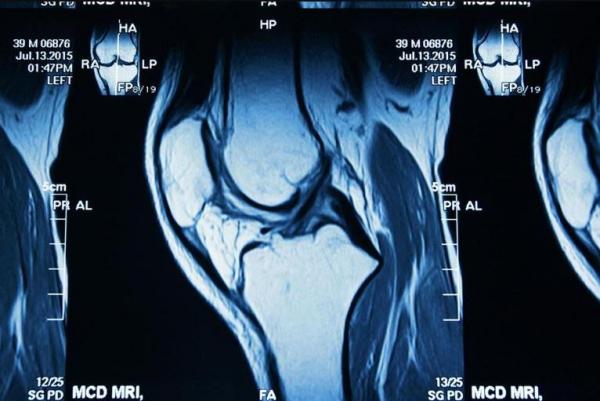

Las técnicas de imagen tienen una enorme importancia en el campo de las urgencias y las emergencias, y en los cuidados críticos. Estas situaciones constituyen una parte sustancial de la actividad de cualquier servicio de diagnóstico por imagen, y requieren un manejo clínico eficiente, con diagnósticos correctos y decisiones terapéuticas realizadas de manera oportuna. En pocas actividades médicas como en las urgencias, las emergencias y los cuidados críticos, es tan importante la interrelación entre el clínico y el especialista en imagen.

El objetivo general del Diplomado en Imagen Clínica de la Patología Aguda del Aparato Locomotor en Urgencias y Cuidados Críticos es completar el itinerario educativo, convirtiendo a los médicos clínicos y a los radiólogos en maestros en la utilización de las técnicas de imagen para el manejo de los pacientes con

necesidad de atención urgente o de cuidados críticos, sea cual sea el medio en el que se encuentren

El Diplomado en Imagen Clínica en Imagen Clínica de la Patología Aguda del Aparato Locomotor en Urgencias y Cuidados Críticos, está orientado a facilitar la actuación del médico y aumentar su capacidad para diagnosticar y tratar a los pacientes en situación de emergencia o que requieran cuidados críticos